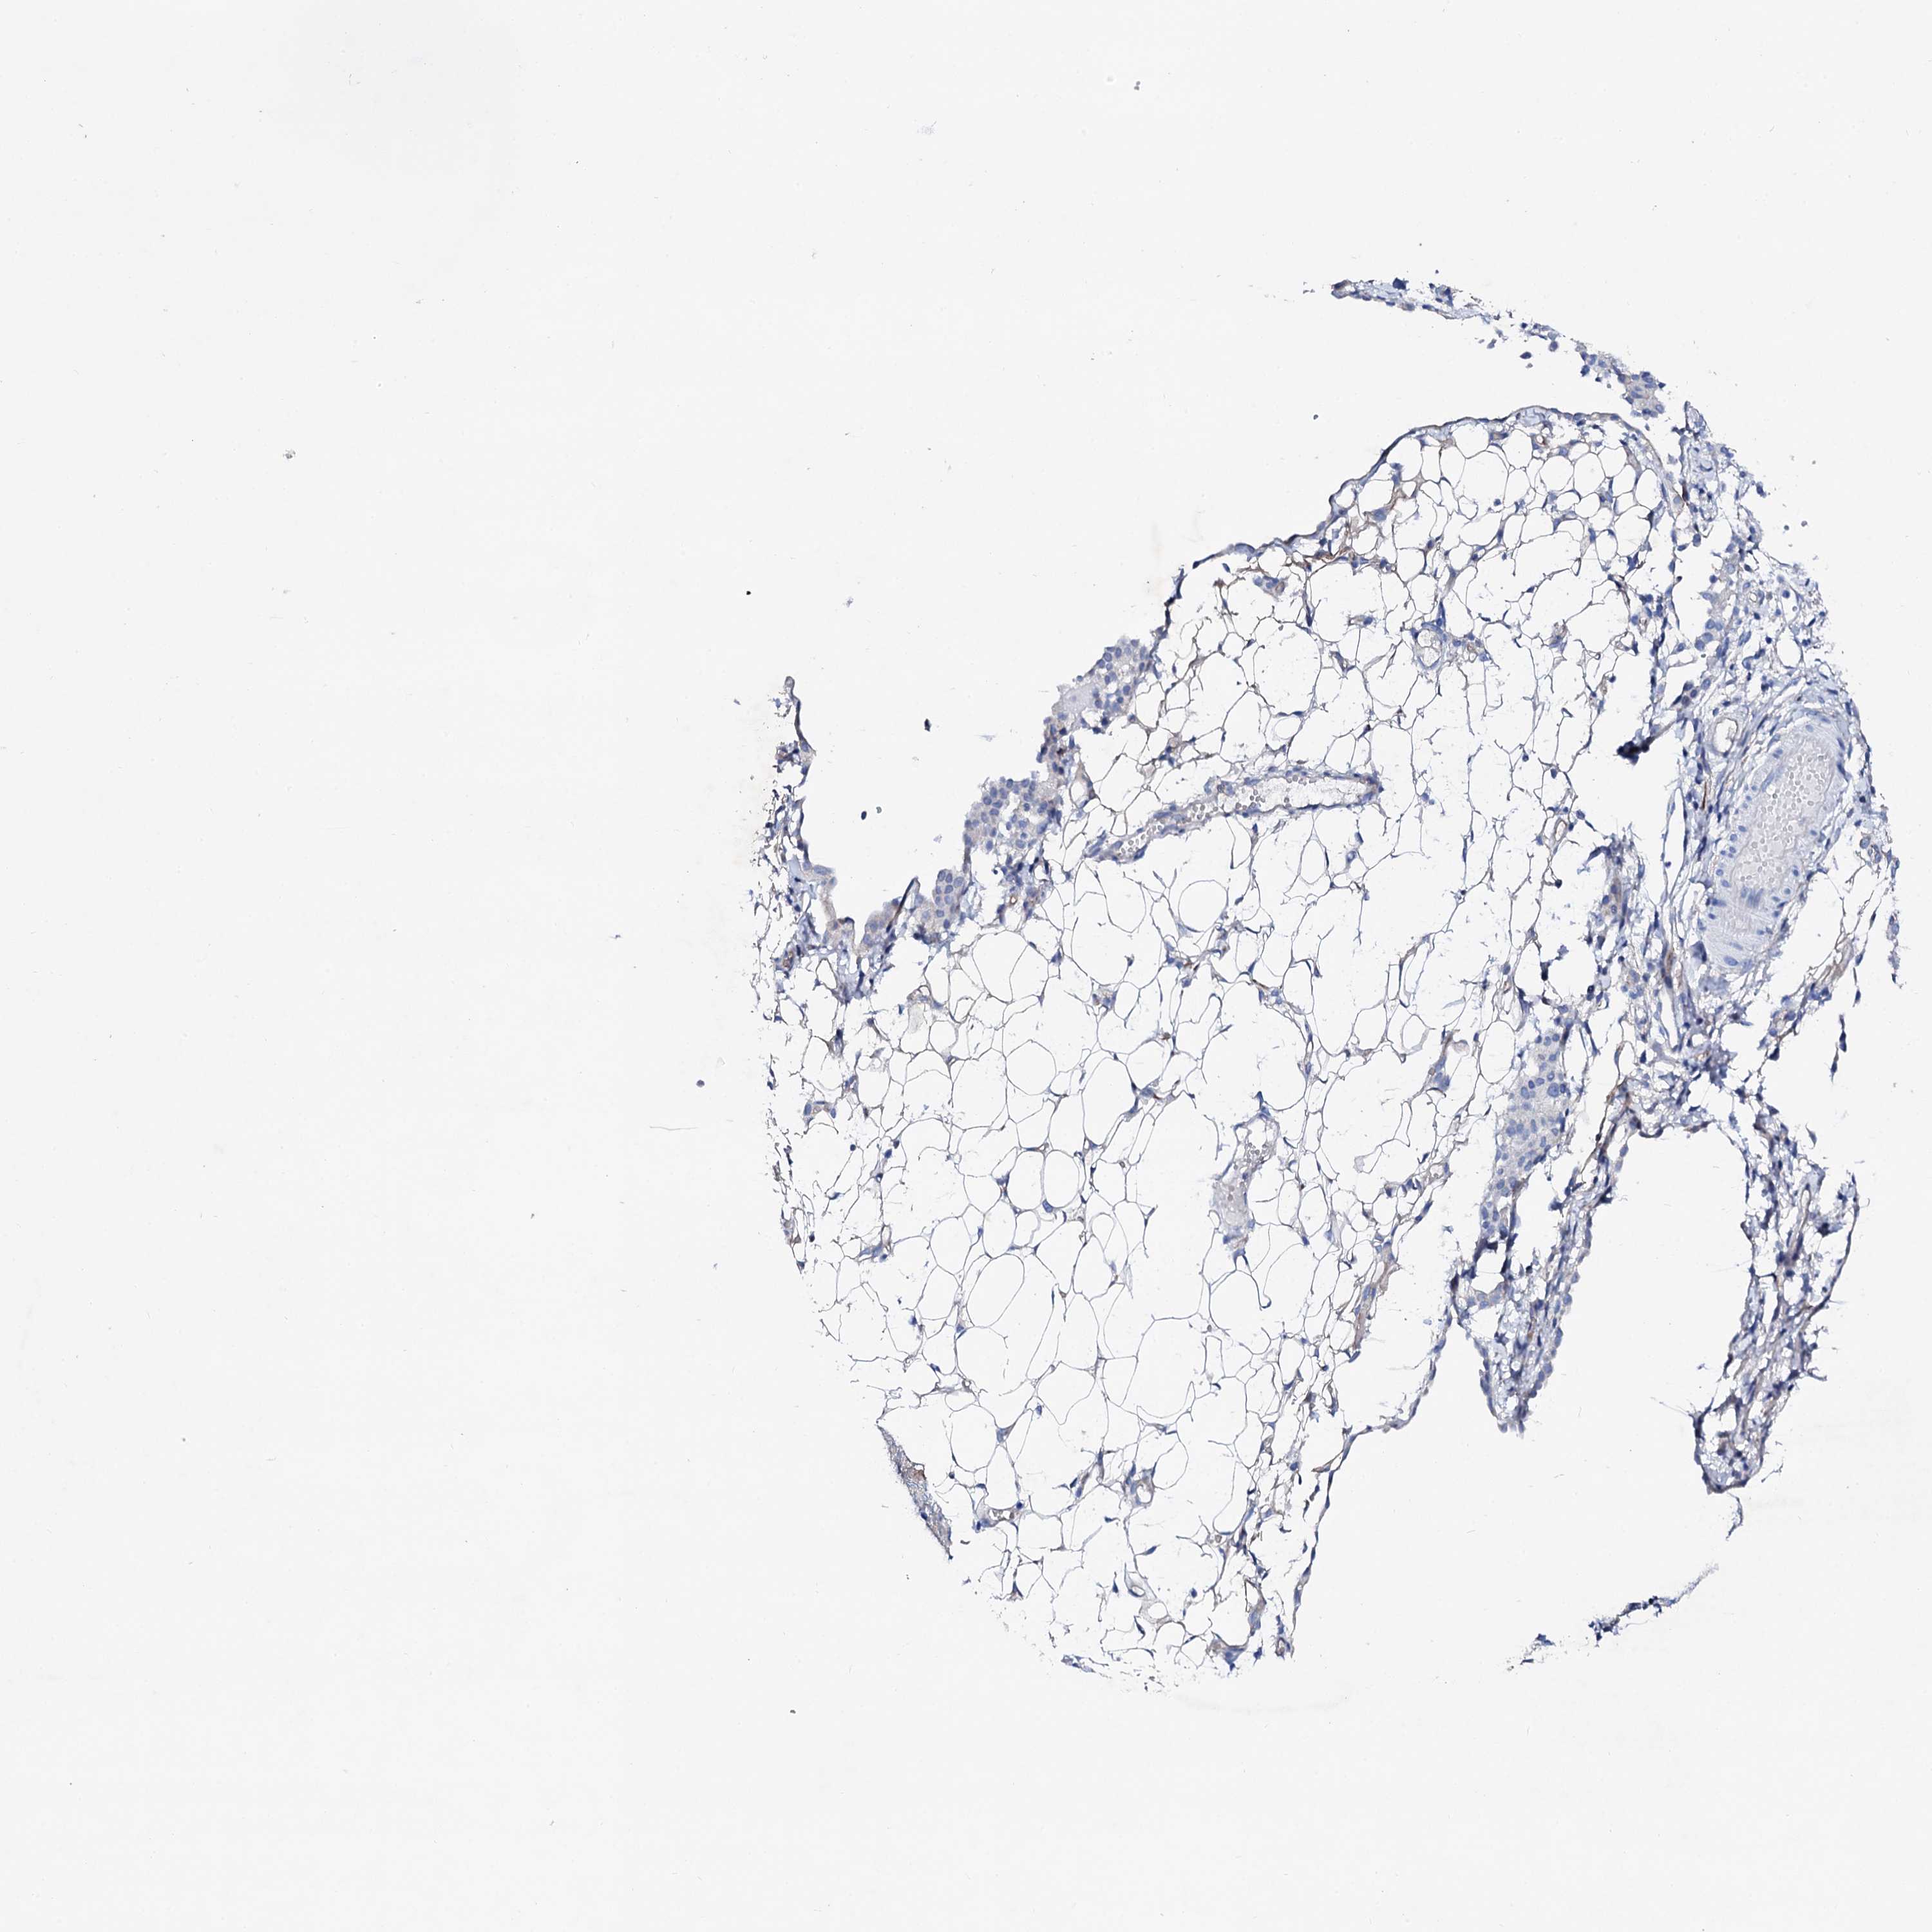

OVARIAN CANCER - Protein expressioni

A mouse-over function shows sample information and annotation data. Click on an image to view it in a full screen mode. Samples can be filtered based on level of antibody staining by selecting one or several of the following categories: high, medium, low and not detected. The assay and annotation is described here.

Note that samples used for immunohistochemistry by the Human Protein Atlas do not correspond to samples in the TCGA dataset.

Antibody stainingi

Antibody staining in the annotated cell types in the current human tissue is reported as not detected, low, medium, or high, based on conventional immunohistochemistry profiling in selected tissues. This score is based on the combination of the staining intensity and fraction of stained cells.

Each image is clickable and will lead to virtual microscopy that enables deeper exploration of all samples and also displays staining intensity scores, fraction scores and subcellular localization as well as patient and tissue information for each sample.

Antibody HPA038226

Antibody HPA058226

Cystadenocarcinoma, serous, NOS

Carcinoma, endometroid

Cystadenocarcinoma, mucinous, NOS

Carcinoma, NOS